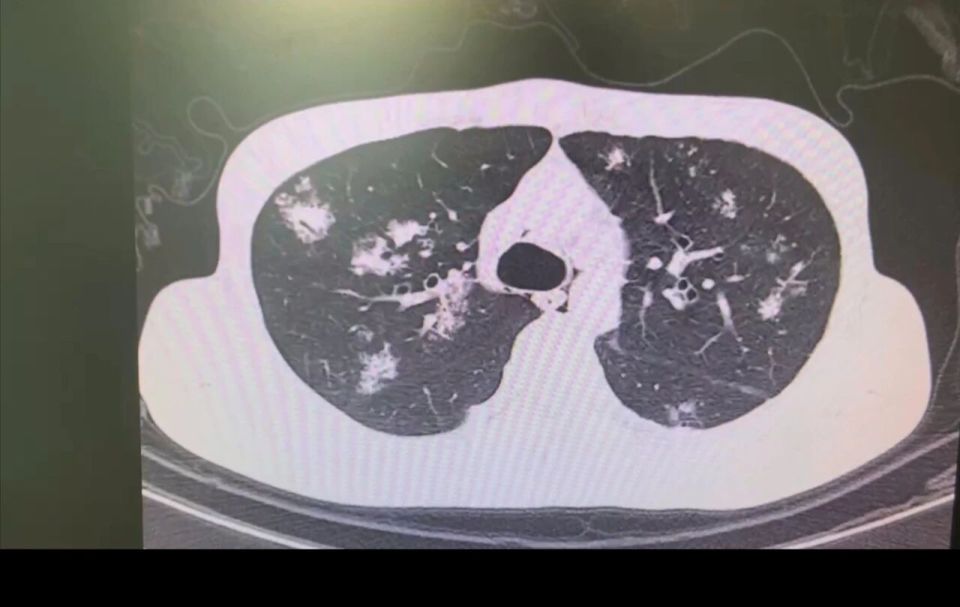

图片